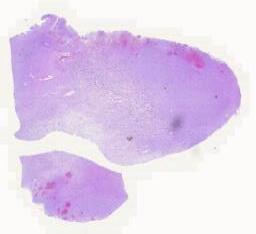

临床资料: 男性,6岁,左侧额叶占位 主诉:右侧手脚活动不协调2周 病史:2周前患者无明显诱因出现右侧手脚活动不协调,表现为右侧上下肢体乏力,当地医院行头部CT及MRI示左侧额叶占位和右侧颞叶占位。查体:右侧肢体肌力4-级,左侧肢体肌力5级,生理反射存在,病理反射未引出。 头颅MRI: 左侧额叶见团块状囊实性肿块影,较大层面约7.2×6.7×6.3cm,实性部分呈稍长T1信号影,水抑制序列呈稍高信号,弥散受限,增强后病灶呈不规则花环状强化,病灶周围见片状长T1长T2水肿带,邻近侧脑室明显受压变窄,中线结构向右侧偏移。右侧颞部颅板下见一大小约2.4×1.9cm稍长信号结节,在水抑制序列上呈高信号,弥散受限,增强后病灶呈明显强化,似见脑膜尾征。 术中所见(左额叶占位切除术): 病变主体位于左侧额叶、基底节,灰红色、质软,局部呈鱼肉状,内侧达侧脑室外侧壁,病灶与周围脑组织分界不清,血供略丰富。

大体所见: 灰红灰白不整形组织多块,总体积2.5cm×2.0cm×0.5cm。